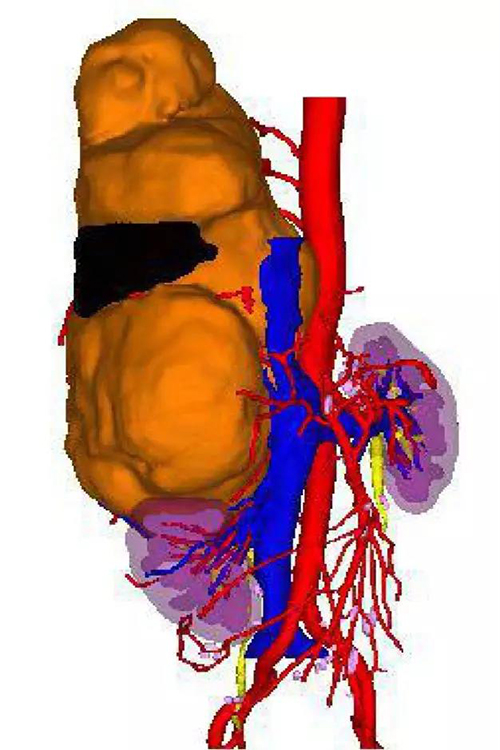

右侧腹膜后肿瘤三维重建可视图

患者为男性,67岁,右侧腰部疼痛、胸闷1月余。泌尿外科主任吕家驹在接诊这位由胸外科专家介绍来的患者时非常吃惊,这是一例临床上很少见的巨大右侧腹膜后间叶源性肿瘤,最大长径超过30cm,肿瘤约1/2突入胸腔,与右侧肾脏、肝脏、大血管、脊柱关系密切。